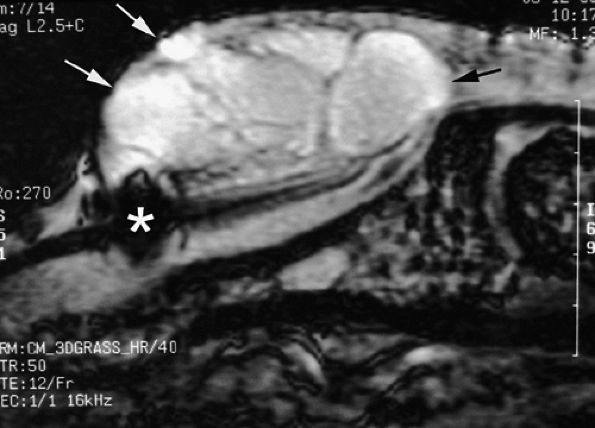

FIGURE 11.8 ● MR arthrography of nondisplaced tear of the UCL of the first MP joint. Coronal (A) and sagittal multiplanar reformatted (MPR) (B) T1-weighted fat-suppressed 3D gradient-echo images showing an oblique tear (asterisk) of the UCL without avulsion. Thearrows mark the distal (black) and proximal (white) aspects of the torn UCL. The sagittal MPR slice is defined along the course of the UCL. MC, metacarpal; AA, adductor aponeurosis.